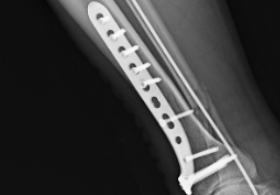

近日,41歲的貨車司機韓師傅在搬運貨物時,因貨物太重不慎摔倒,右腿扭傷。同事們立即撥打120,將他送往紹興袍江醫(yī)院急診科。到達醫(yī)院時,韓師傅的右小腿已經(jīng)明顯腫脹變形。急診科醫(yī)生迅速為他安排了檢查,結(jié)果顯示"右側(cè)脛腓骨遠段多發(fā)骨折"。作為家中的頂梁柱,這個診斷讓韓師傅心情沮喪——他擔心漫長的康復期會影響工作,更擔心留下后遺癥。骨科李志龍主任醫(yī)師團隊會診后,立即為韓師傅制定了詳細的手術方案。次日,在椎管內(nèi)麻醉下,李志龍主任主刀為韓師傅施行了"右脛腓骨2025-11-10